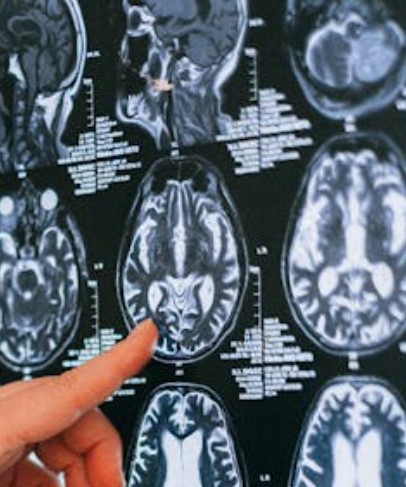

뇌경색은 뇌로 가는 혈류가 막혀 산소와 영양 공급이 끊기는 병이에요. 증상이 나타났을 때 신속히 대처해야 피해를 줄일 수 있어요.